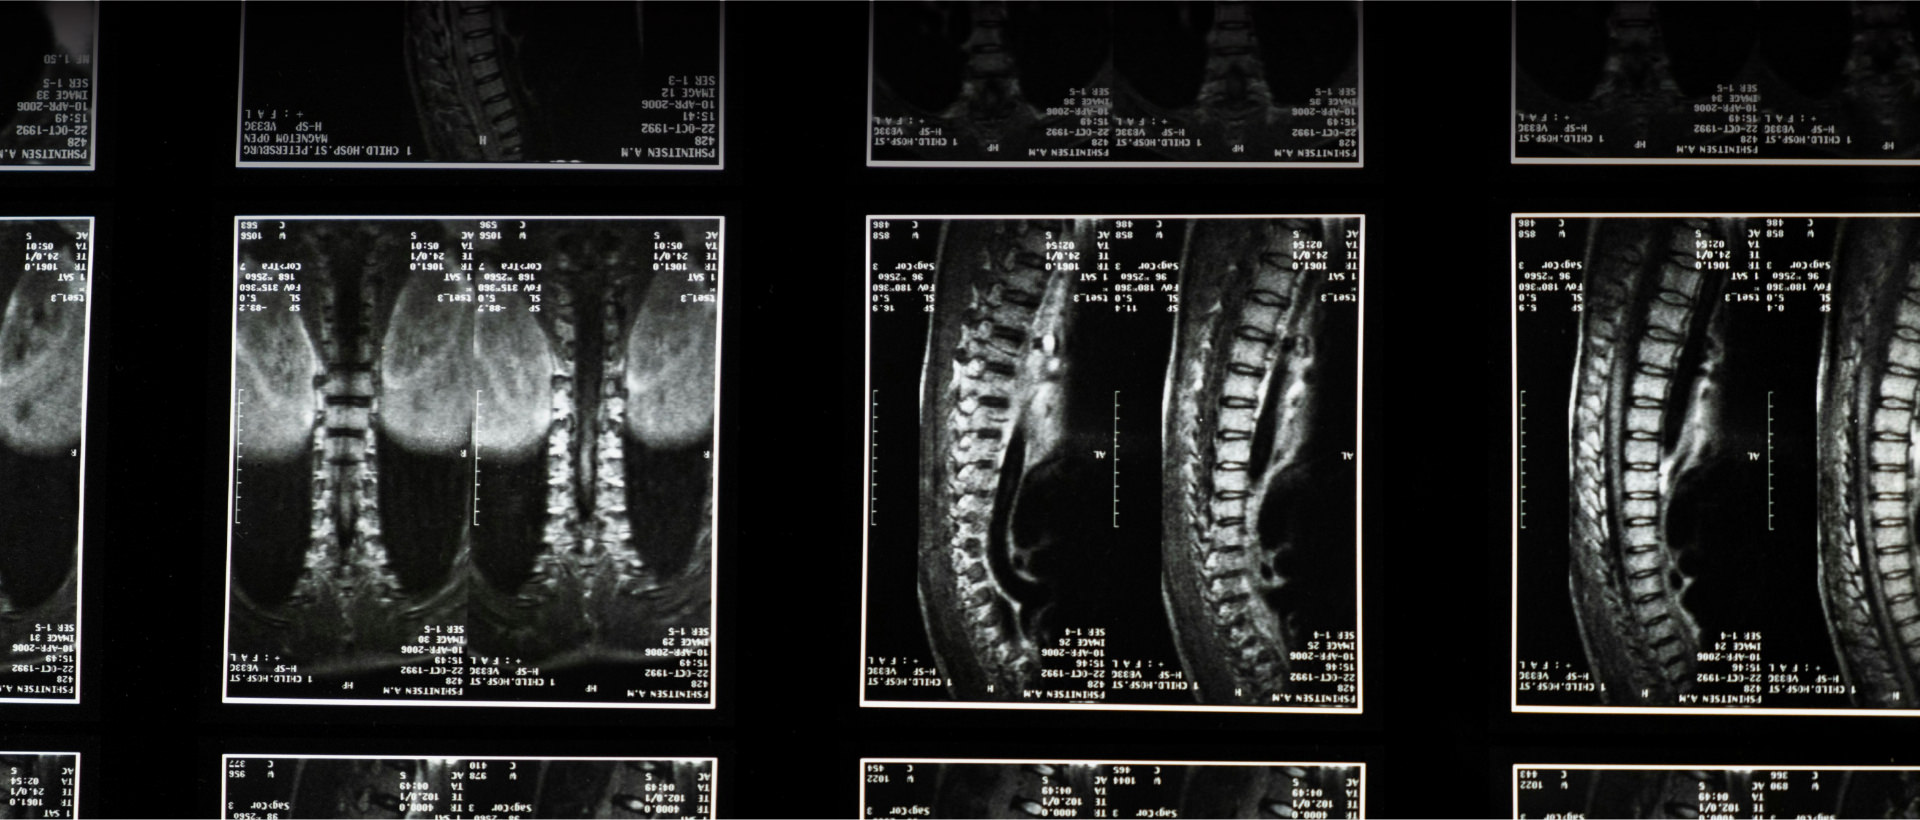

A detecção precoce das doenças vasculares cerebrais é essencial. Exames como angiotomografia, ressonância magnética e angiografia cerebral são indispensáveis para identificar alterações com precisão e definir a melhor conduta terapêutica. Em muitos casos, um diagnóstico ágil pode evitar sequelas graves e garantir uma recuperação completa.